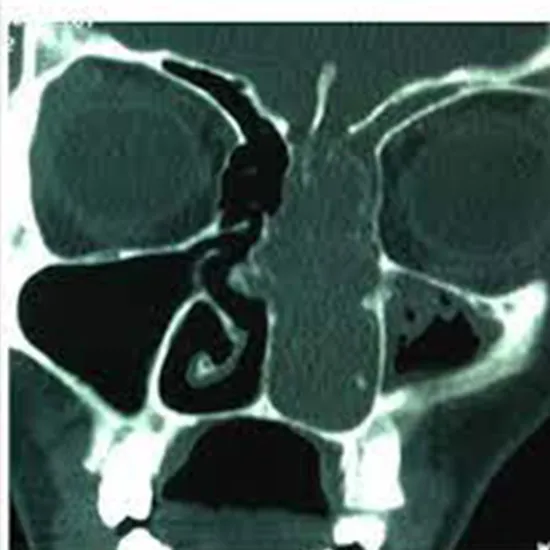

CECT (Contrast Enhanced Computed Tomography) PNS(Para Nasal Sinus) Coronal is a non-invasive imaging procedure that uses contrast media and X-beam to create images of the paranasal sinus. Contrast media enhance visibility and help in the effective diagnosis of the problem.

Why is CECT PNS(Para-Nasal Sinus) Coronal Done?

• Doctors recommend this scan to evaluate PNS and diagnose underlying issues such as

• Inflammation, tumour and fluid accumulation in the sinus

• Fracture or trauma

• Increase in thickness of tissue

• Presence of abnormal mass growth

• Birth defects